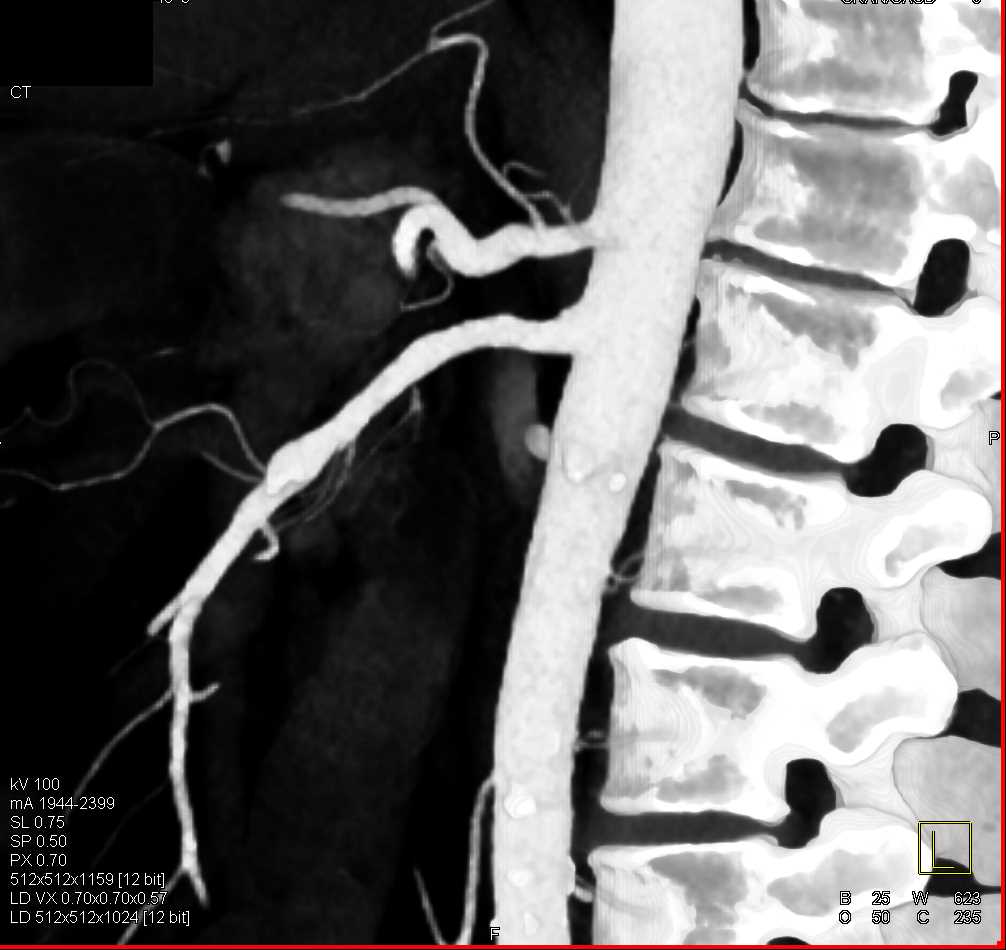

Diagnosis

SMA Stenosis